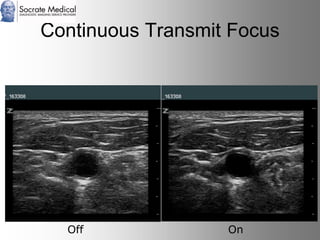

Il documento presenta la tecnologia della zone sonography, che promette una rivoluzione nel campo degli ultrasuoni, superando i limiti dei sistemi tradizionali grazie a metodi di acquisizione dati più veloci e una gestione delle informazioni migliorata. Questa tecnologia consente una maggiore definizione dell'immagine, una riduzione degli artefatti e un'ottimizzazione del processo diagnostico, con vantaggi in termini di tempo e costi. Inoltre, il channel domain processing e la zone speed technology offrono applicazioni avanzate e miglioramenti nella sicurezza diagnostica.